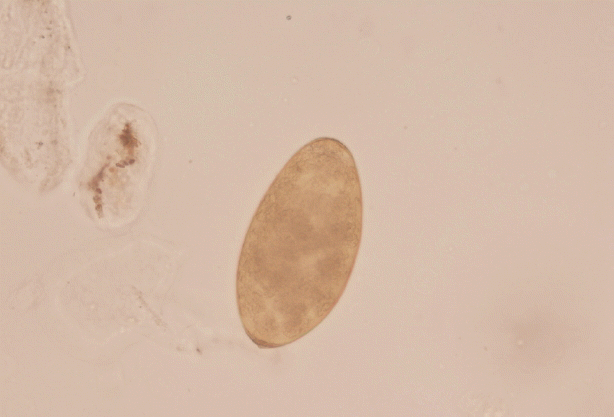

Based on routine, the doctors suspected a parasitic disease for the 4 patients, who were referred to Fujian Center for Control and Prevention. By stool sample analysis using water sedimentation method, Fasciola spp. eggs were found in Mrs. Xiao and her younger sister. Based on the shape and mean size (143×82 μm), the operculated eggs were identified as Fasciola spp. eggs (Fig. 3). Since the other 2 family members also consumed water dropwort and showed stomachache, all of them were referred to NIPD for further diagnosis.